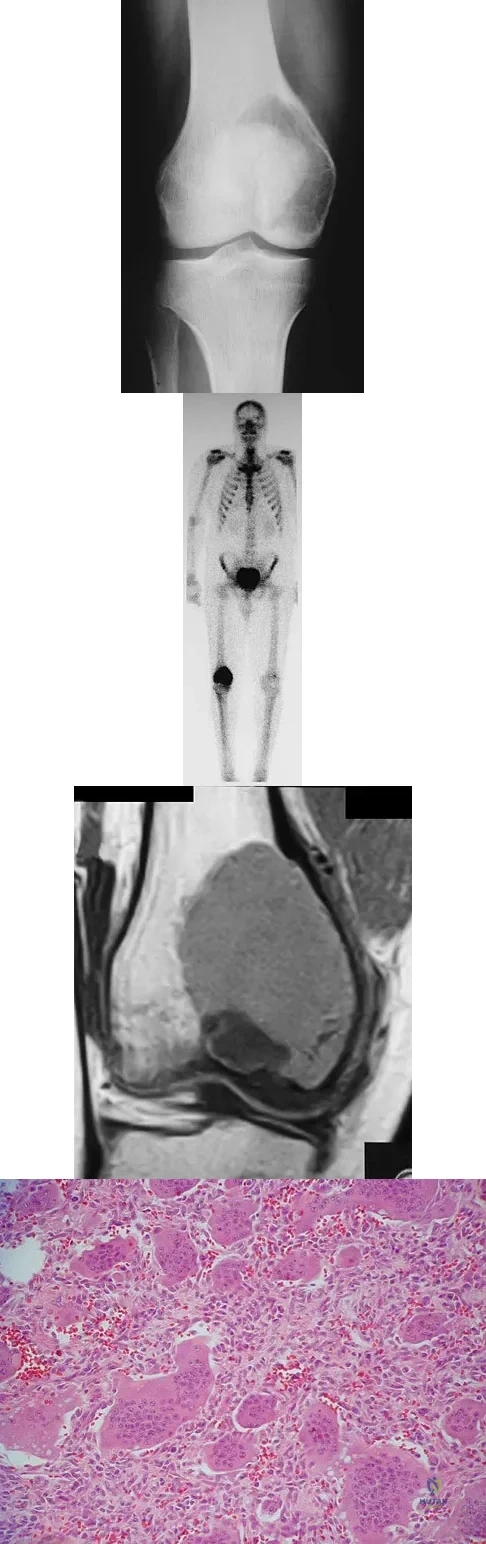

A 16-year-old girl has had painless swelling in her posterior left arm for the past 4 months. A radiograph, MRI scans, and an incisional biopsy specimen are shown in Figures 43a through 43d. What is the cytogenetic translocation most commonly associated with this tumor?

Explanation

This is a case of synovial sarcoma. The radiograph shows some soft-tissue swelling in the upper arm. The MRI scans show a lesion that has increased signal on T2-weighted images and low signal on T1-weighted images. There is a suggestion of a large cystic component to this lesion. The pathology shows a biphasic population of cells, a spindle cell component, and an epithelioid component. Up to 20% of synovial cell sarcomas have areas of cyst formation. The most common cytogenetic translocation with synovial cell sarcoma is X; 18. The 11; 22 translocation is most commonly associated with Ewing's sarcomas; the 12; 22 translocation is most commonly associated with clear cell sarcomas; the 2; 13 translocation is most commonly associated with alveolar rhabdomyosarcomas, and the 12; 16 translocation is most commonly associated with myxoid liposarcomas. Kawai A, Woodruff J, Healey JH, et al: SYT-SSX gene fusion as a determinant of morphology and prognosis in synovial sarcoma. New Engl J Med 1998;338:153-160.

A 10-year-old child has leg discomfort with activity. A radiograph, bone scan, and biopsy specimen are shown in Figures 1a through 1c. What is the most likely diagnosis?

Explanation

The ground glass appearance on the radiograph, the hot bone scan, and histologic findings of bony spicules without osteoblastic rimming in a background of bland fibrous tissue all suggest fibrous dysplasia. Stress-related pain is common with activity because of the dysplastic bone. Parosteal osteosarcomas are surface lesions. Simple cysts, aneurysmal bone cysts, and eosinophilic granuloma are all possible radiographically; however, the histology is most consistent with fibrous dysplasia. Harris WH, Dudley HR Jr, Barry RS: The natural history of fibrous dysplasia: An orthopaedic, pathological and roentgenographic study. J Bone Joint Surg Am 1962;44:207.

A 19-year-old woman has a painful right knee. A radiograph, MRI scan, CT scan, and histopathologic specimen are shown in Figures 24a through 24d. What is the most likely oncologic stage of the lesion?

Explanation

The patient has a high-grade osteosarcoma of the distal femur with a skip lesion, and pulmonary metastasis is seen on the CT scan. This corresponds to a stage III lesion according to the Musculoskeletal Tumor Society System as adopted from Enneking.